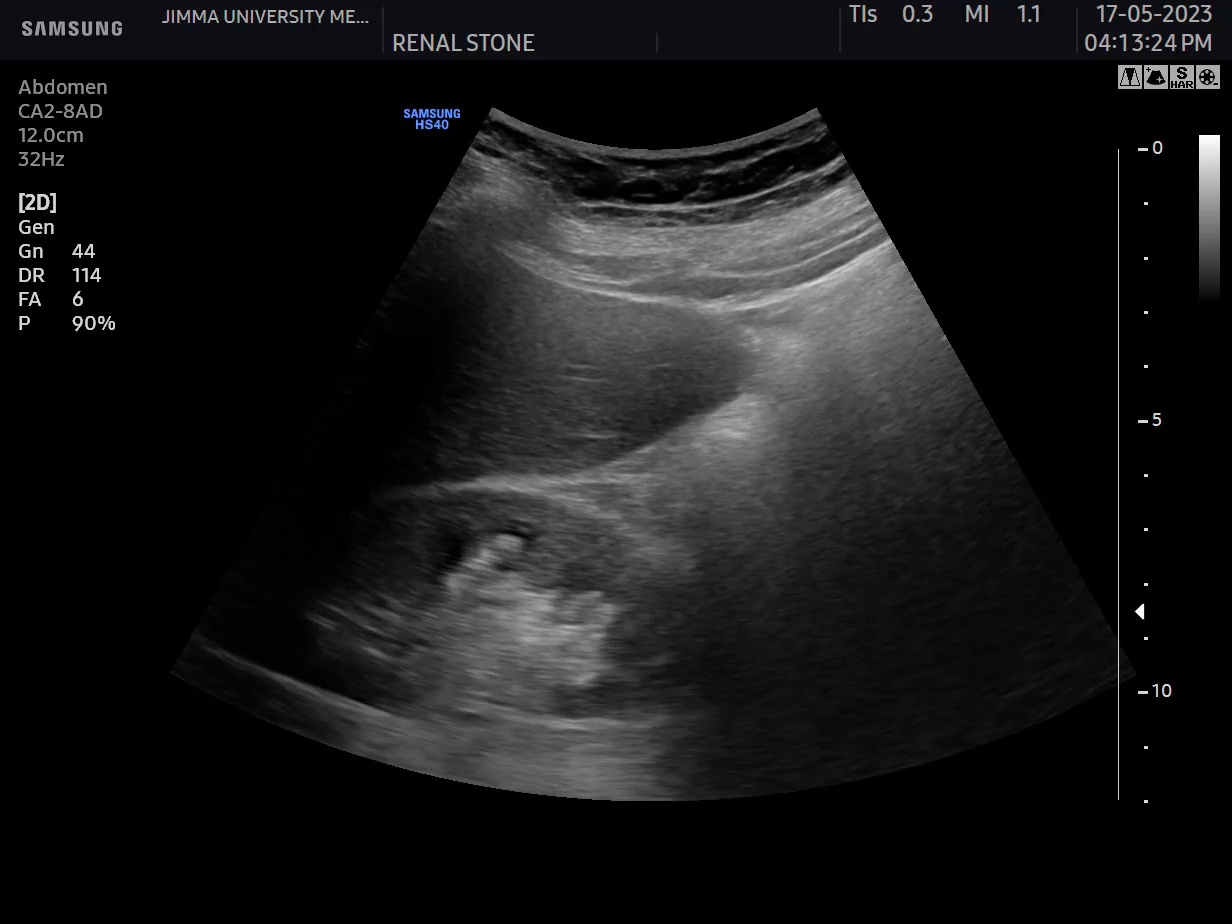

kidney stone labelling with shadow and with out shadow Object Detection What Does A Shadow On Kidney Mean My mum is 65 and has had a pain under her ribs since last summer, i begged her to go to the gp but she was to. If your gp refers you to a specialist because they think you could have kidney cancer, you’ll. it is true that a ct will pick up a tumour, but it may also. What Does A Shadow On Kidney Mean.